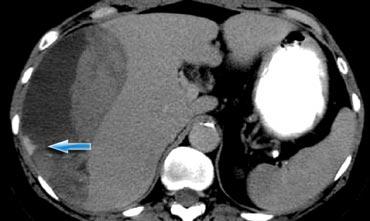

Bên trái là một bệnh nhân khác với chấn thương xuyên thấu do vết đâm dao ở hông.

CT cho thấy rõ ràng rằng tổn thương giới hạn trong khoang sau phúc mạc với khối máu tụ nhỏ quanh thận.

Không có dấu hiệu vi phạm phúc mạc và trên hình ảnh pha muộn (không hiển thị) không có hiện tượng thoát thuốc cản quang từ hệ thống thu thập nước tiểu.

Bệnh nhân này sẽ được điều trị bảo tồn không phẫu thuật